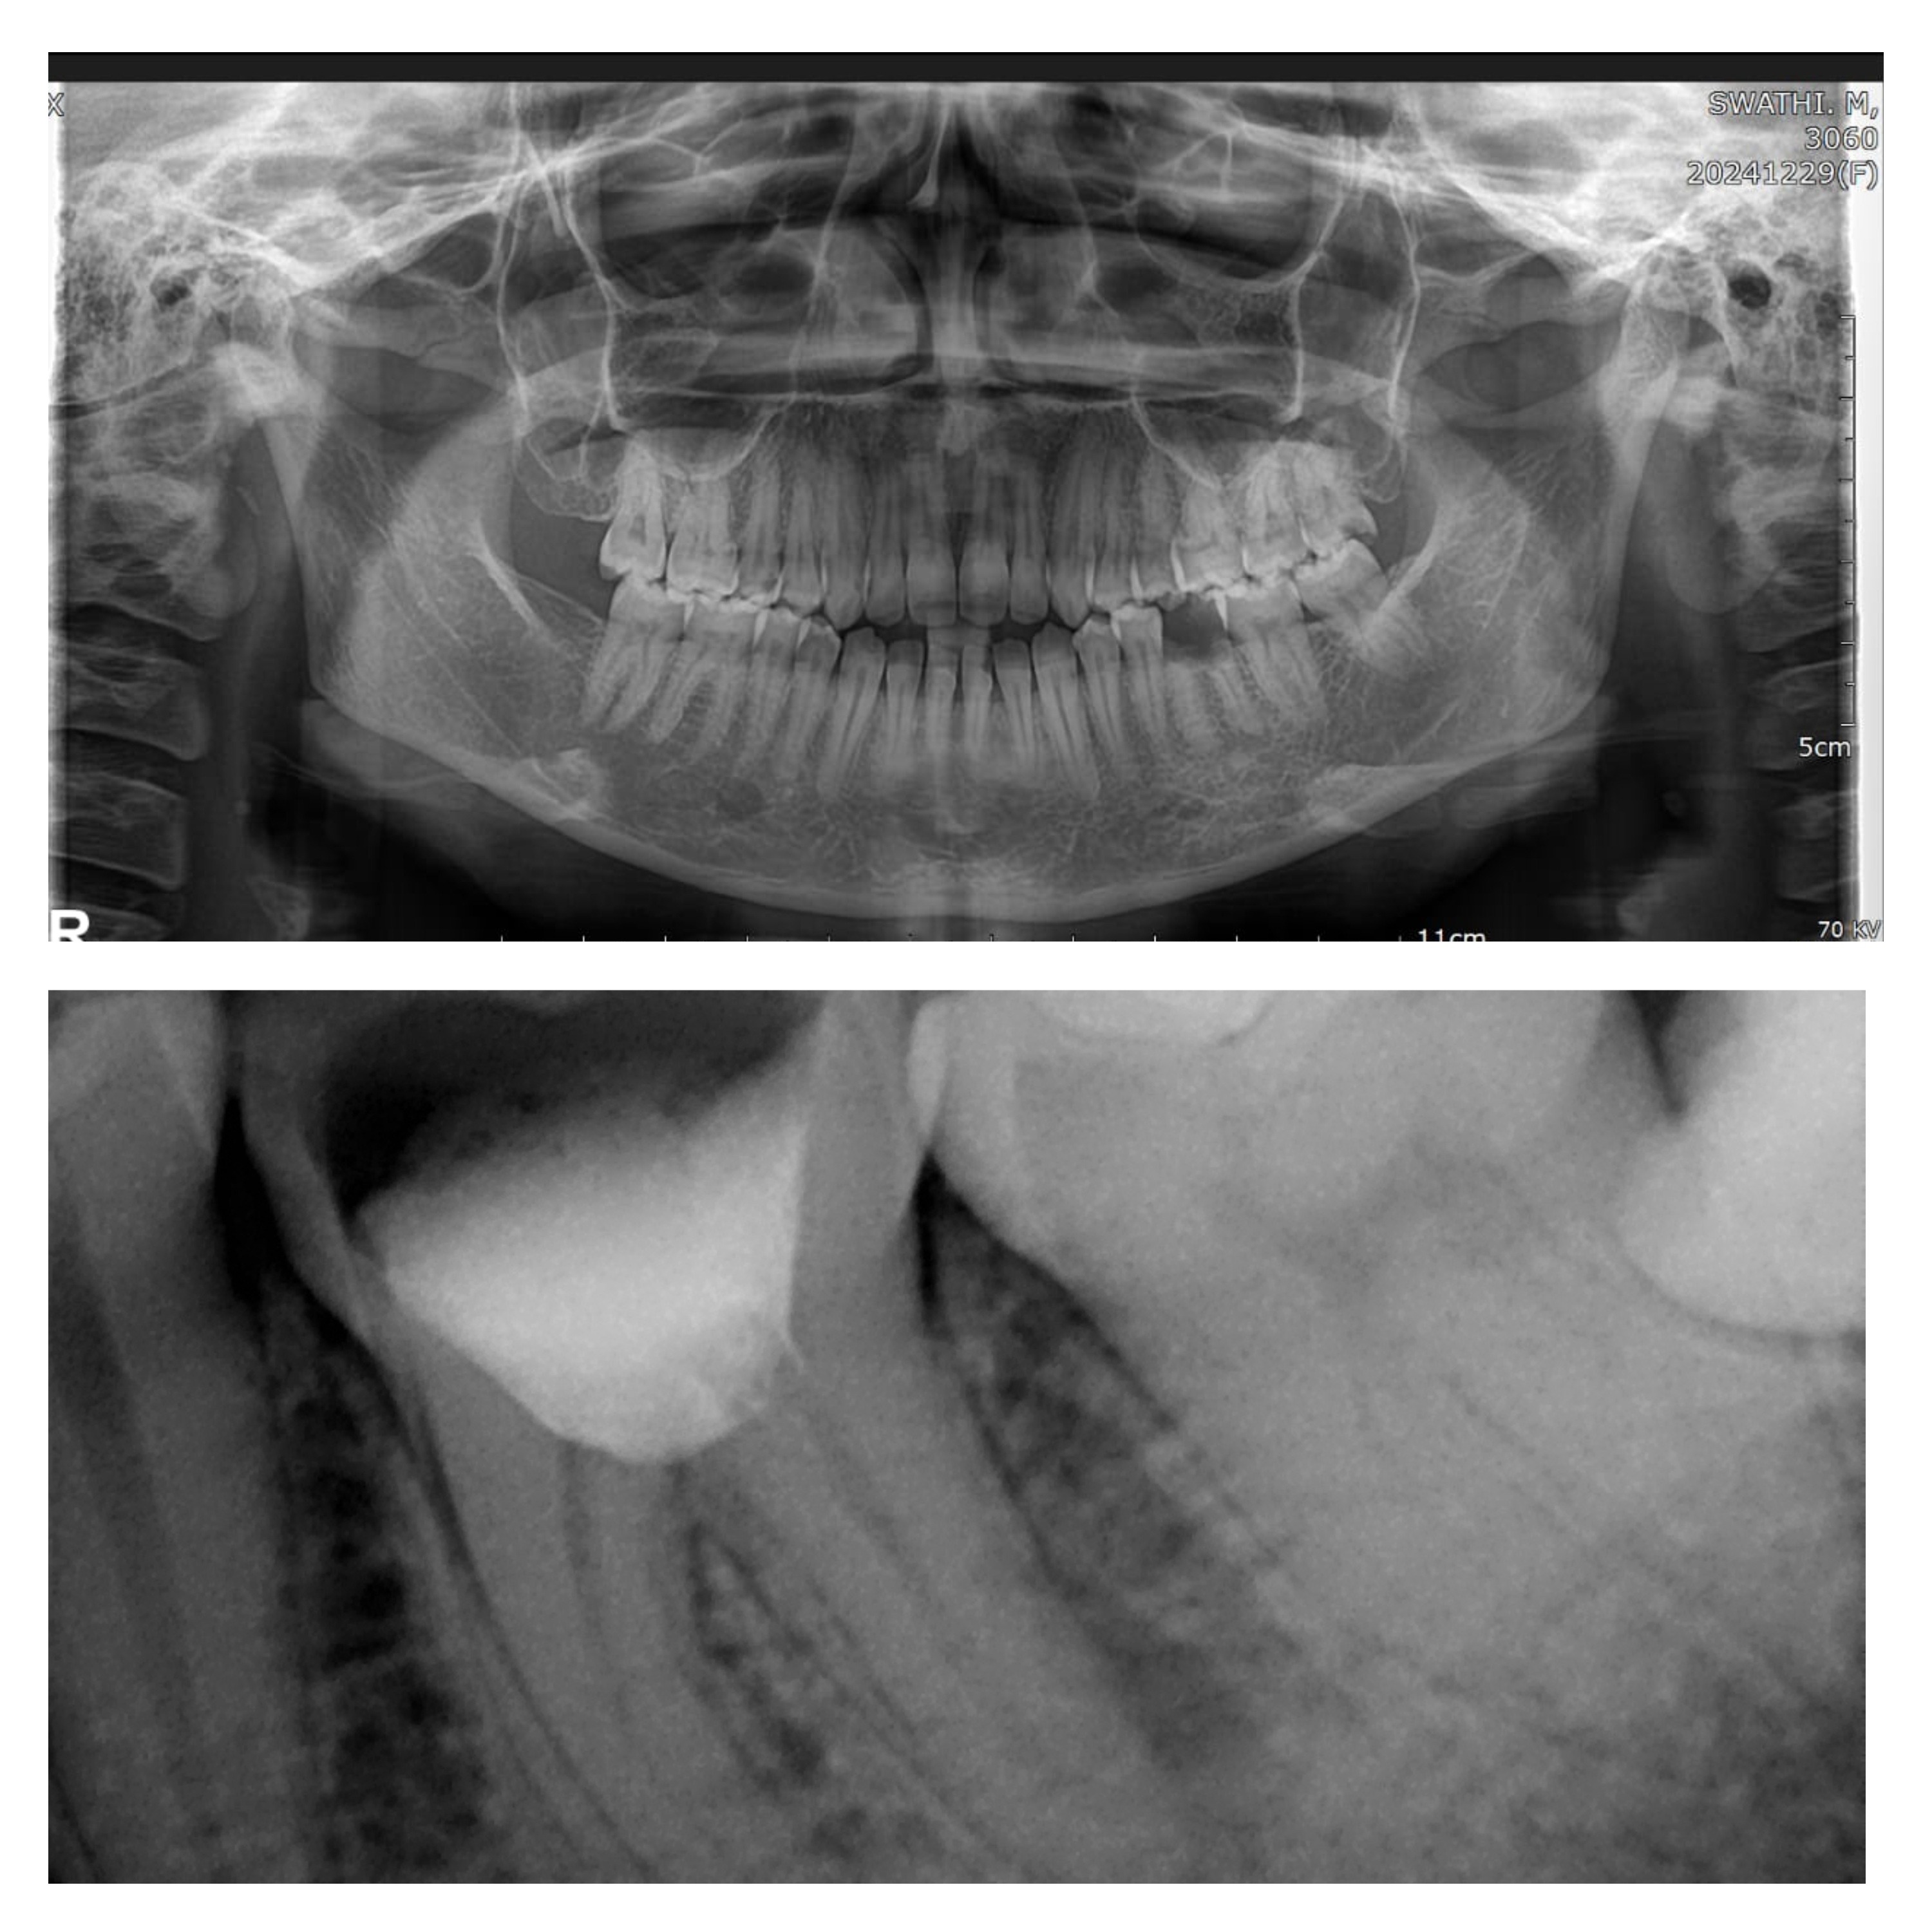

DIFFERENCE BETWEEN OPG AND RVG, ROOTZ DENTAL CARE NAVALUR 1. Full Mouth vs. Single Tooth – OPG captures the entire jaw, while RVG focuses on a specific tooth or small area. 2. Purpose – OPG is used for overall dental evaluation, while RVG is used for precise diagnosis of cavities, root canals, and fractures. 3. Image Type – OPG provides a panoramic (wide) view, whereas RVG gives a detailed close-up of a tooth. 4. Radiation Exposure – OPG has low radiation, but RVG has even lower since it targets a small area. 5. Detail & Clarity – RVG offers high-resolution images, while OPG provides a broader but less detailed view. 6. Speed & Processing – OPG takes 10-15 seconds for a full-mouth scan, while RVG provides instant real-time images. 7. Usage in Dentistry – OPG is used for orthodontics, implants, and jaw evaluation, while RVG is for root canal treatments and cavity detection. 8. Equipment Needed – OPG requires a special panoramic machine, while RVG uses a small digital sensor placed inside the mouth. 9. Patient Comfort – OPG is non-invasive and easy, while RVG may cause slight discomfort due to the sensor inside the mouth. 10. Digital vs. Film – OPG can be film-based or digital, whereas RVG is purely digital with real-time enhancements. To know more contact us at Rootz Dental care Navalur